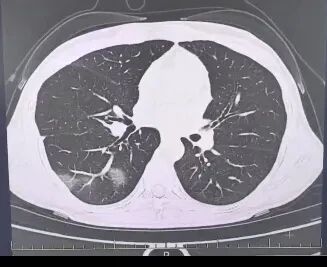

呼吸内科医师了解到她口服速福达抗流感病毒后仍反复发热,并咳出黄色浓痰,立即安排了相关检查。结果情况反而进一步加重:好几叶肺叶都出现了“白肺”现象,指间血氧饱和度只有88%,血心肌酶谱、肌钙蛋白的指标、肝功能的指标也出现了明显的异常。

图源:杭州市第三人民医院微信公众号